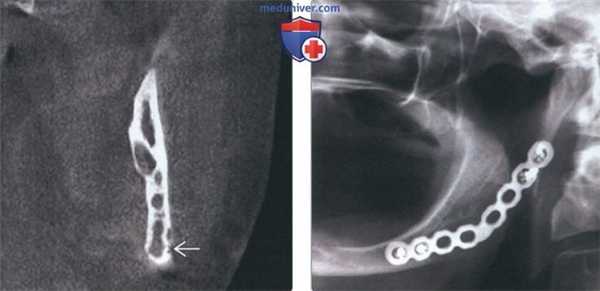

(Слева) Рентгенография в ПЗ проекции: умеренно агрессивный, вспученный литический диафизарный очаг с псевдотрабекуляцией и патологическим переломом в дистальном отделе. Данные признаки не специфичны. Двумя наиболее вероятными диагнозами являются неоссифицирующая фиброма и десмопластическая фиброма.

(Справа) МРТ, аксиальная проекция, режим Т1: внутрикостный очаг у этого же пациента В, характеризующийся сигналом, интенсивность которого немногим ниже сопряженной мышцы. Визуализируется выраженная вспученность малоберцовой кости. Такие признаки неспецифичны, однако сигнал очень низкой интенсивности предполагает наличие фиброзного очага.